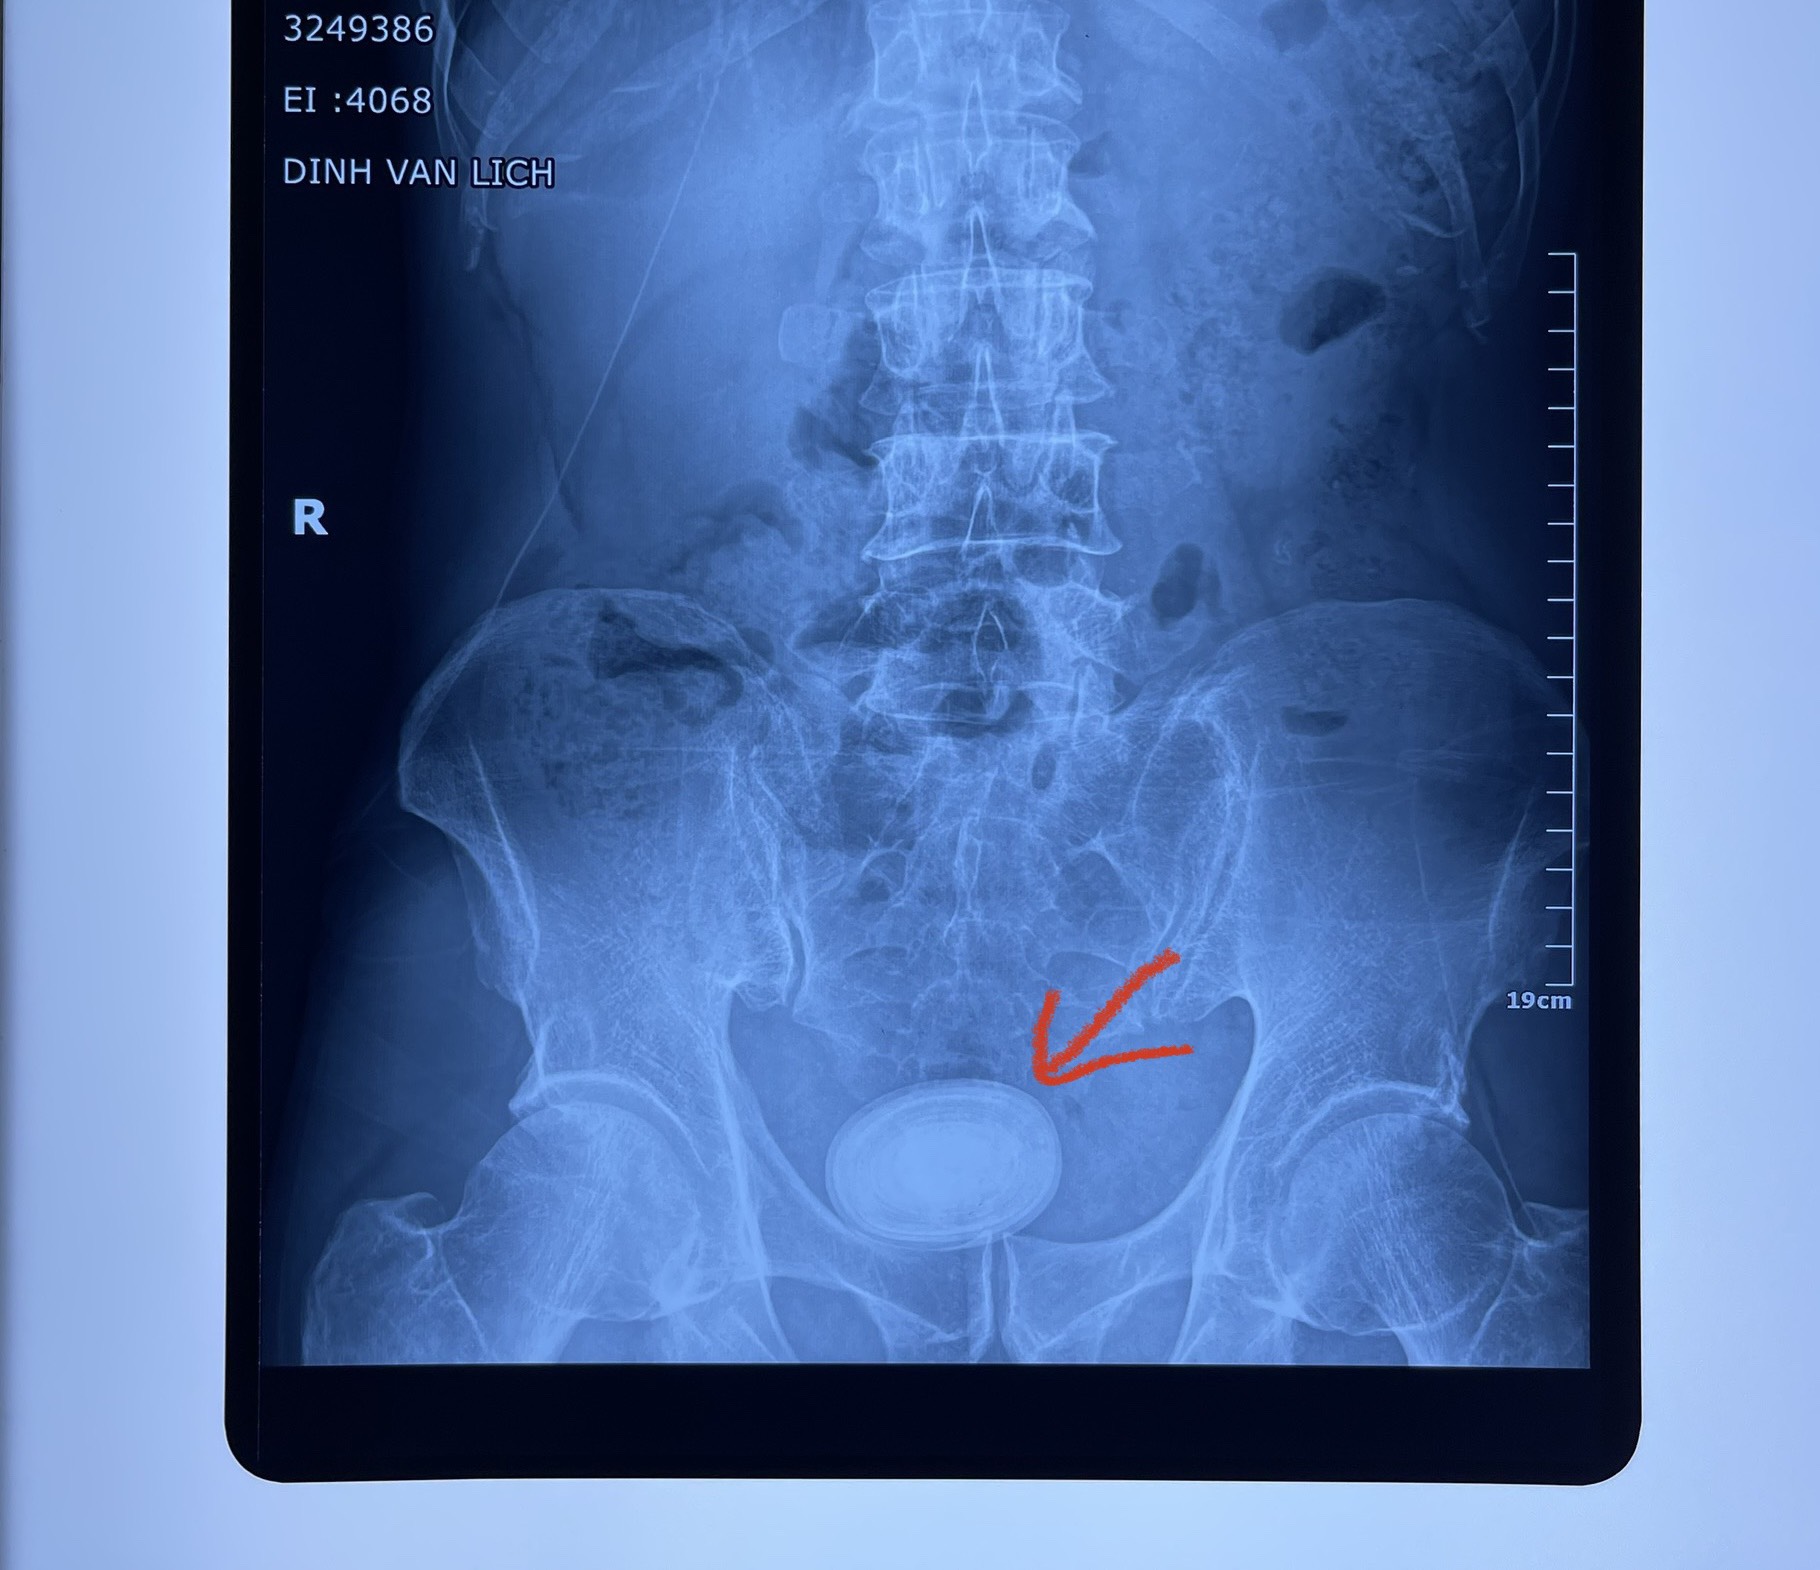

Khi nhập viện, người bệnh được các bác sĩ thăm khám và chỉ định cận lâm sàng. Kết quả siêu âm và chụp CT-Scanner cho thấy thận phải có sỏi kích thước 4x10mm; bàng quang thành dày lan tỏa, có sỏi kích thước 56x62x38mm, phì đại tuyến tiền liệt.

Các bác sĩ chẩn đoán người bệnh Nhiễm khuẩn tiết niệu do sỏi / U phì đại tiền liệt tuyến đươc điều trị hết tình trạng nhiễm khuẩn sau đó được chỉ định phẫu thuật tán sỏi bàng quang bằng laser và nội soi cắt u phì đại tiền liệt tuyến bằng máy đơn cực. Sau hơn 2 giờ, ca phẫu thuật thành công. Sau 5 ngày điều trị, tình trạng sức khoẻ người bệnh ổn định